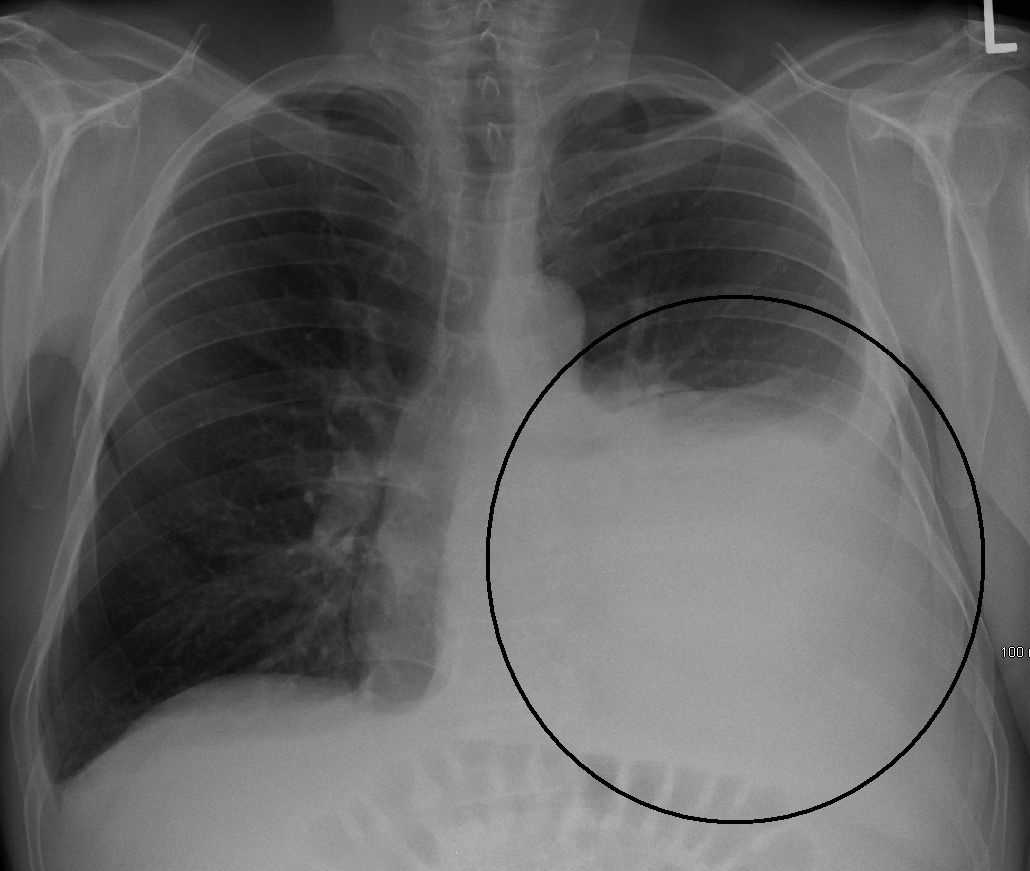

प्ल्यूरल इफ्यूजन का निदान कैसे किया जाता है? (Diagnosis of Pleural effusion)

प्ल्यूरल इफ्यूजन का पता लगाने के लिए डॉक्टर शरीर की जांच करते हैं और मरीज का पारिवारिक इतिहास भी देखते हैं। इस बीमारी को जानने के लिए कुछ टेस्ट कराए जाते हैं:

- सीने का एक्स रे